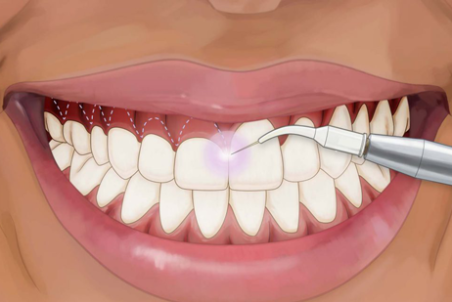

درمان گیاهی عفونت لثه

عفونت لثه بر اثر بیماری های لثه ایجاد می شود که اصطلاحا التهاب لثه یا پریودنتیت می گویند. عفونت لثه امکان دارد به علت سیگار کشیدن، جویدن تنباکو و یا آسیب لثه به وجود آمده باشد که با درمان گیاهی عفونت لثه می توان آن را برطرف نمود.

لیفت لثه؛ مزایا و قیمت آن

بسیاری از افراد از پایین بودن بیش از حد لثهی خود ناراضی هستند و این موضوع زیبایی لبخند آنان را تحت تاثیر قرار داده است. لیفت لثه میتواند گزینه بسیار مناسبی برای این نوع از اختلالات لثهای باشد.